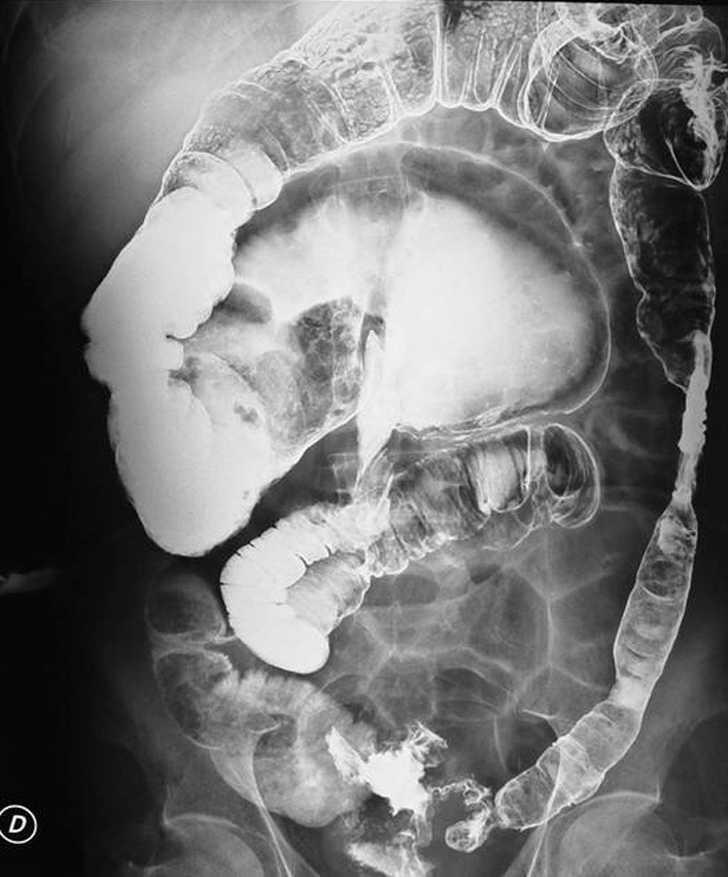

En la radiografía de abdomen se observó una burbuja aérea con dilatación de las asas de delgado, sin neumoperitoneo. La tomografía computarizada (fig. 1) apuntó la sospecha diagnóstica de vólvulo de colon y se indicó enema opaco (fig. 2), que puso de manifiesto un vólvulo cecal, por lo que se procedió a realizar una intervención quirúrgica.

Fig. 2.